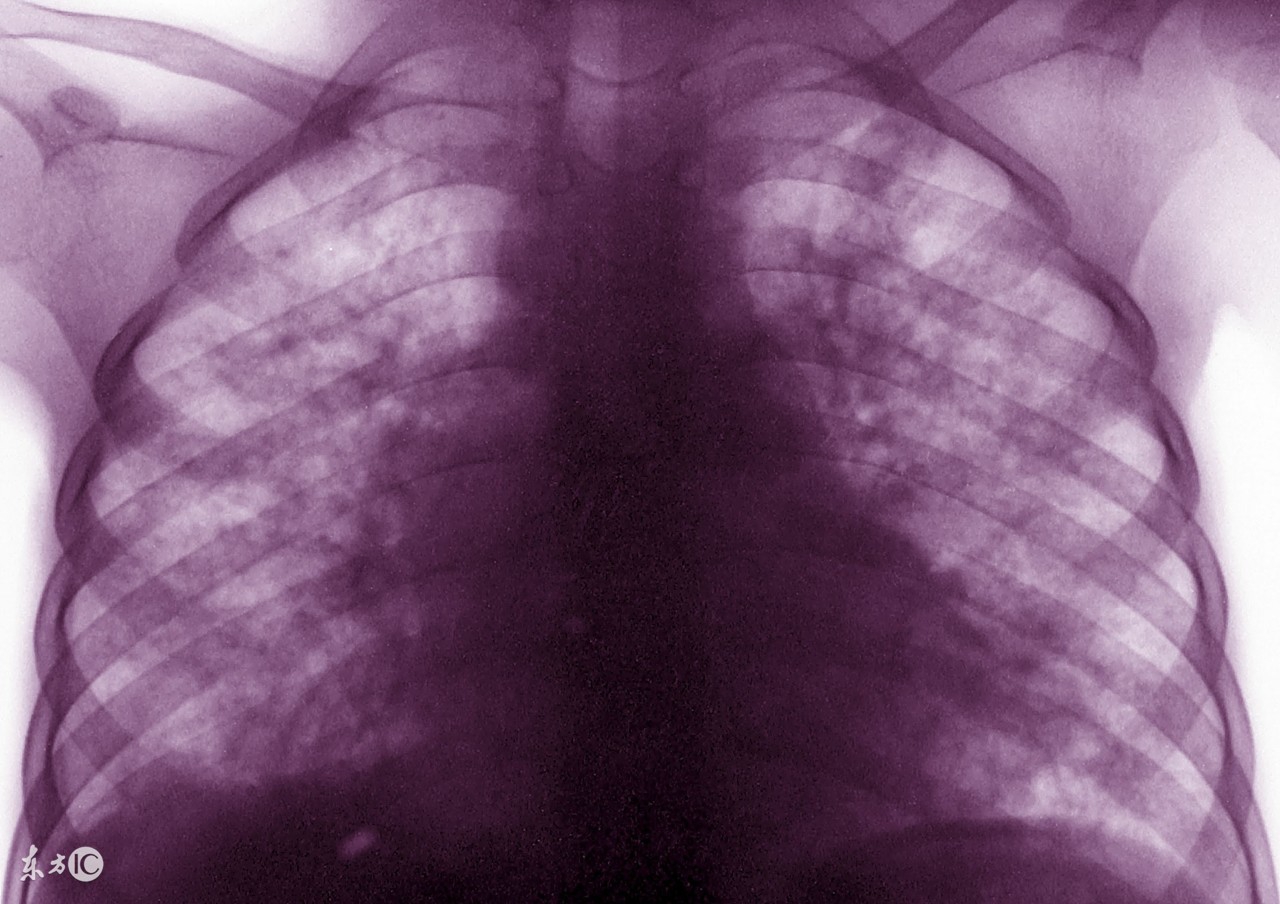

很多肺结核患者在确诊之后,就要马上接受治疗。其实,在临床上,治疗肺结核的方法有很多,很多早期的患者会选择药物治疗,严重的患者就要接受临床治疗了。那么,中医怎样治疗肺结核疾病?其实,治疗方法是根据患者的病情所决定的,中医治疗针对患者的身体损害是很小的。